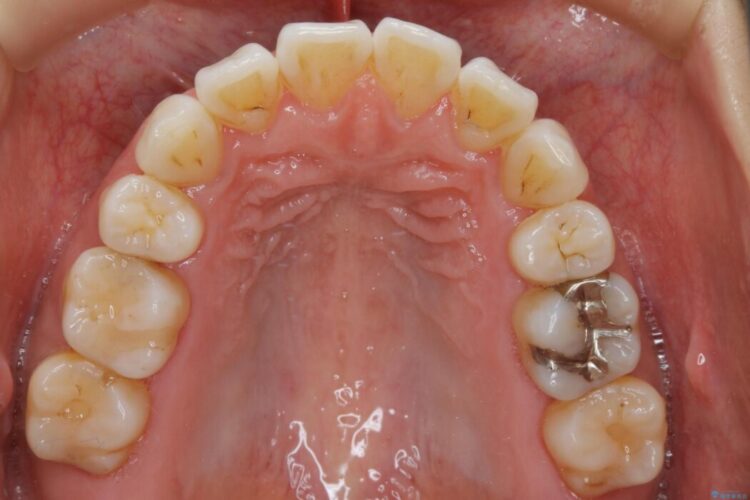

抜歯矯正後の上の前歯の後戻りが気になるとご来院された患者様です。

歯と歯の間を削るのと、歯列のU字型のアーチを僅かに外側に広げる事でスペースを作り、前歯の角度の改善をしました。